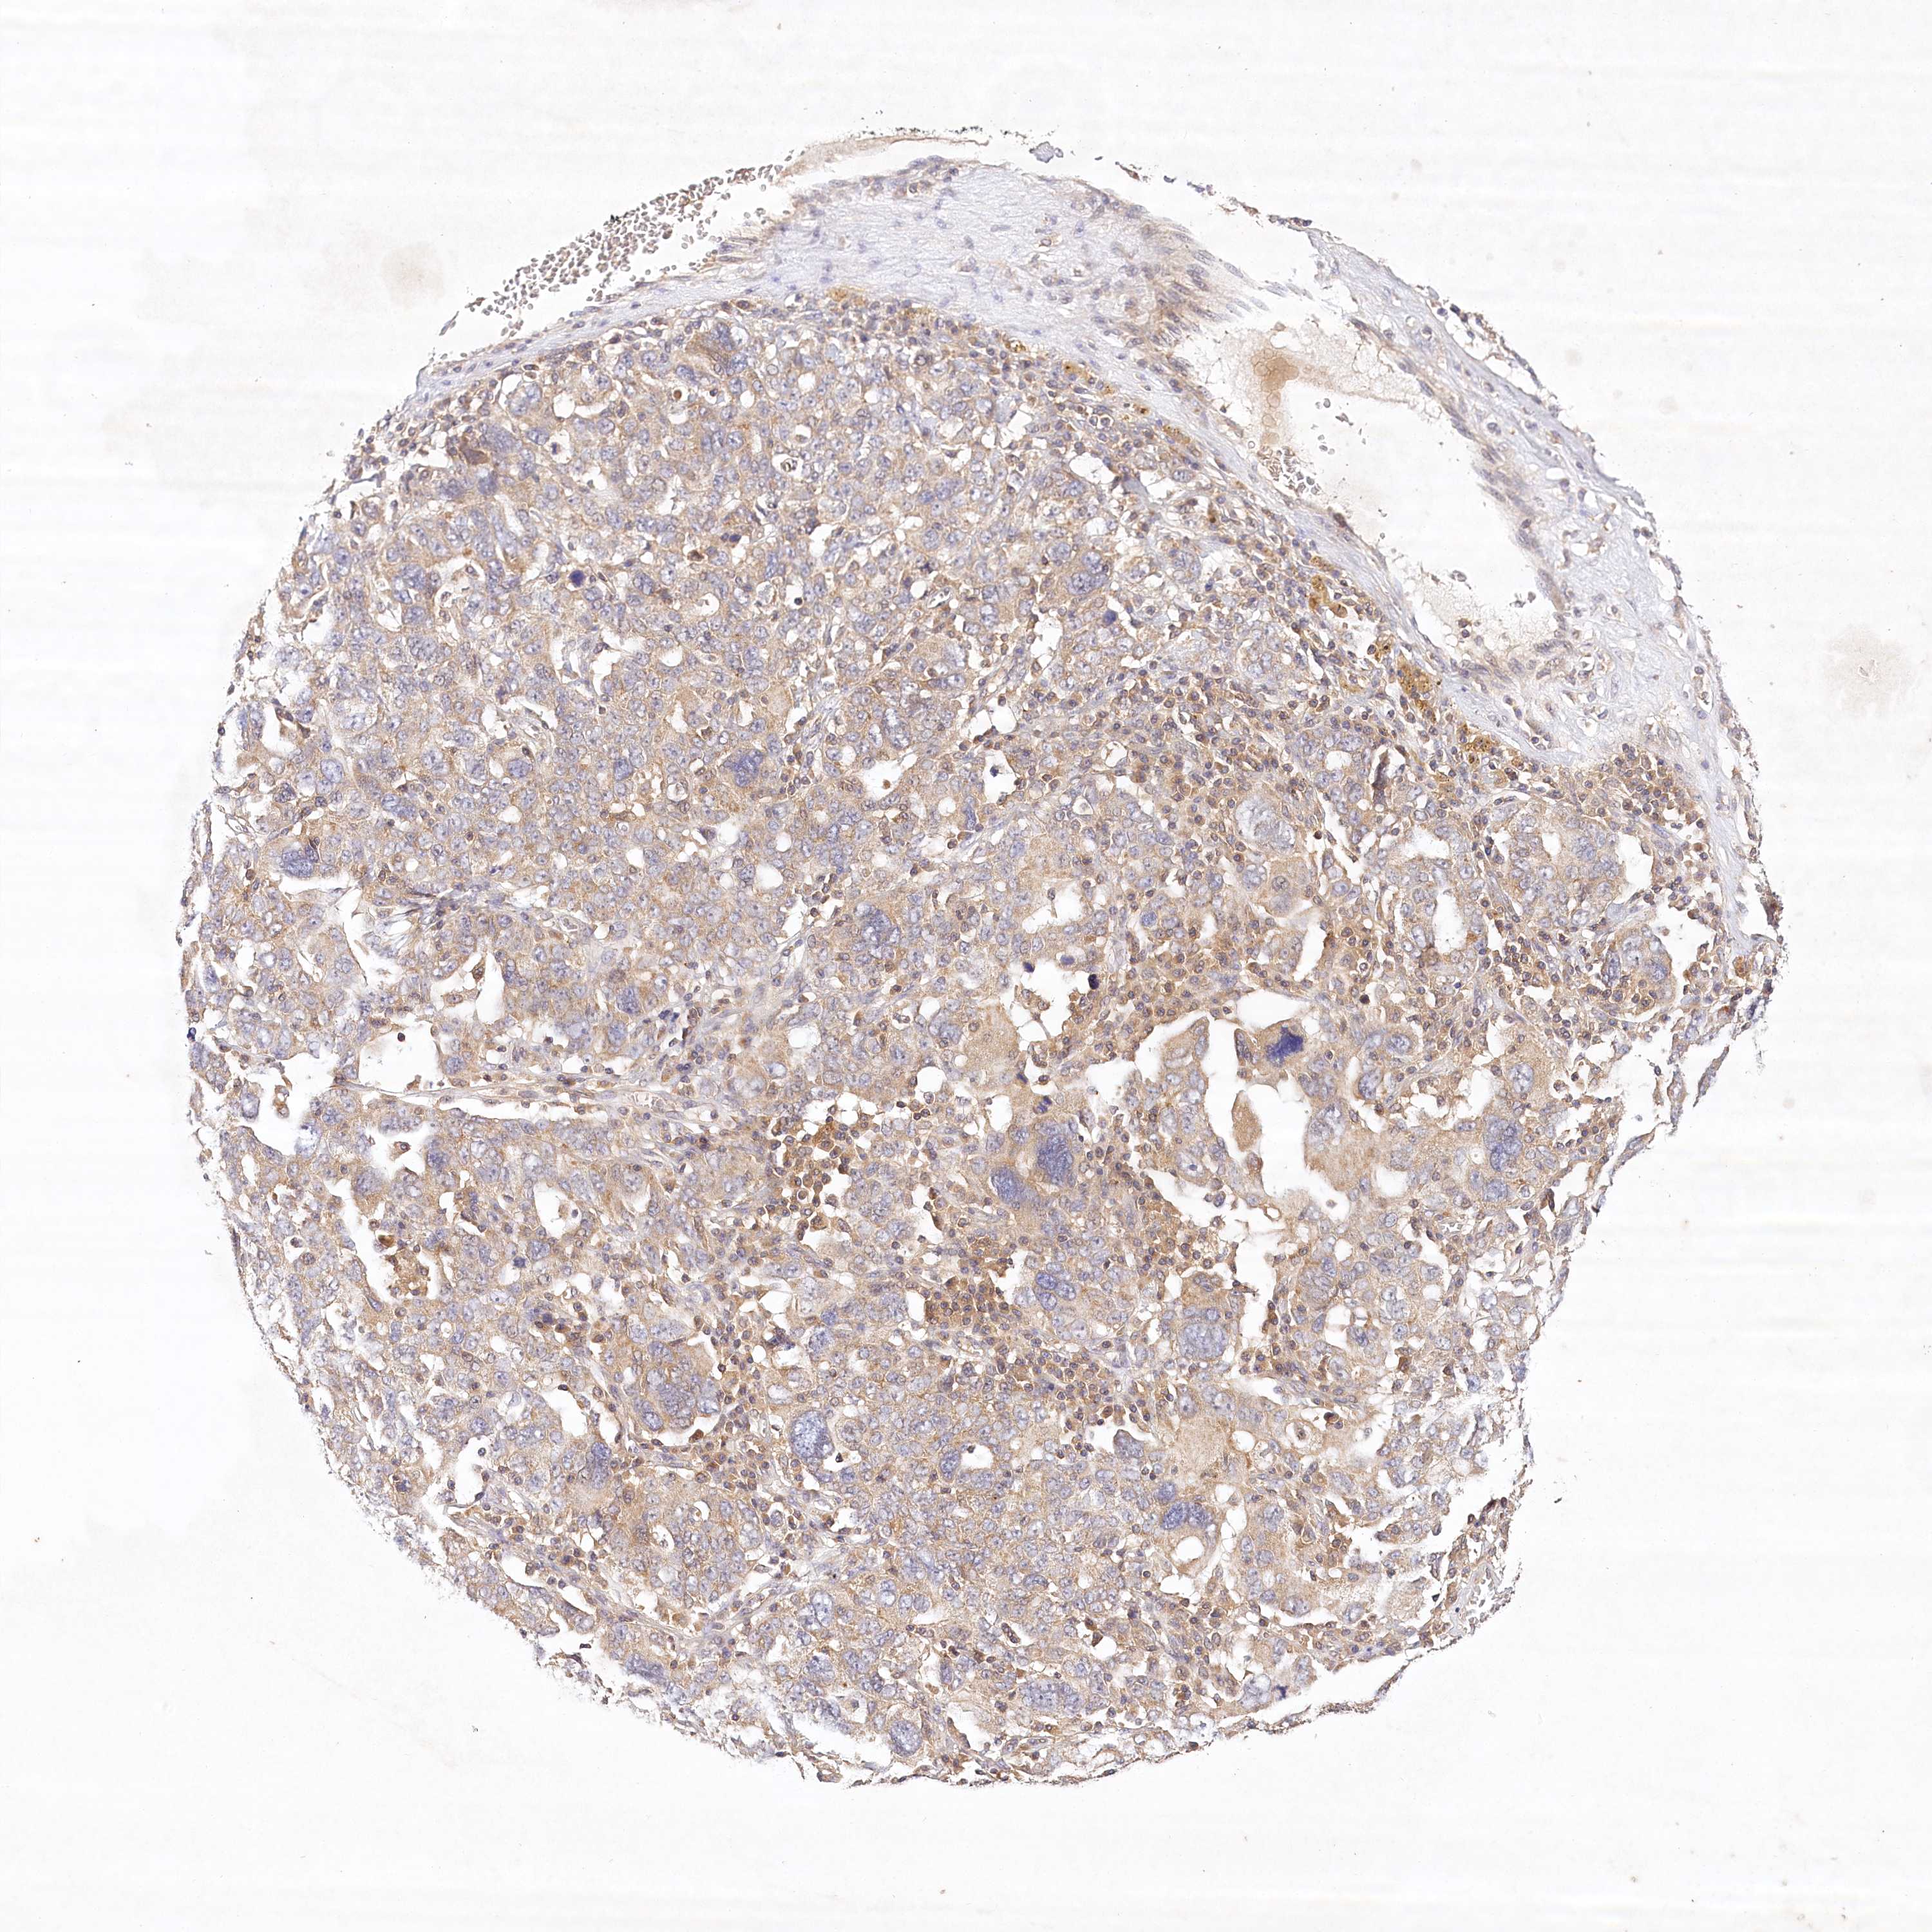

OVARIAN CANCER - Protein expressioni

A mouse-over function shows sample information and annotation data. Click on an image to view it in a full screen mode. Samples can be filtered based on level of antibody staining by selecting one or several of the following categories: high, medium, low and not detected. The assay and annotation is described here.

Note that samples used for immunohistochemistry by the Human Protein Atlas do not correspond to samples in the TCGA dataset.

Antibody stainingi

Antibody staining in the annotated cell types in the current human tissue is reported as not detected, low, medium, or high, based on conventional immunohistochemistry profiling in selected tissues. This score is based on the combination of the staining intensity and fraction of stained cells.

Each image is clickable and will lead to virtual microscopy that enables deeper exploration of all samples and also displays staining intensity scores, fraction scores and subcellular localization as well as patient and tissue information for each sample.

Antibody HPA032060

Antibody HPA032062

Antibody CAB034116

Staining

High

Medium

Low

Not detected

Intensity

Strong

Moderate

Weak

Negative

Quantity

>75%

75%-25%

<25%

None

Location

Nuclear

Cytoplasmic/membranous

Cytoplasmic/membranous,nuclear

Cystadenocarcinoma, serous, NOS

Carcinoma, endometroid

Cystadenocarcinoma, mucinous, NOS

Carcinoma, NOS